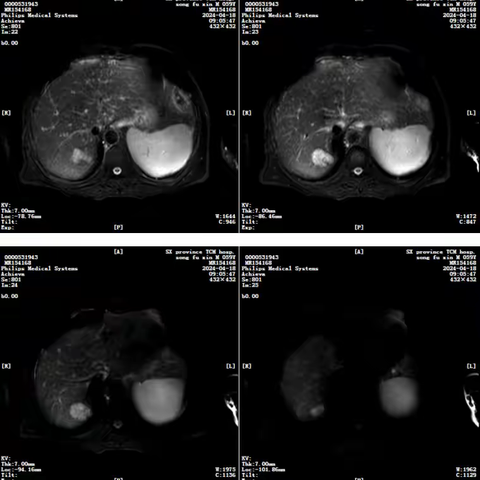

AFP断崖式下降!TACE联合微波消融:肝癌治疗的'精准双杀',肿瘤信号消失无踪!